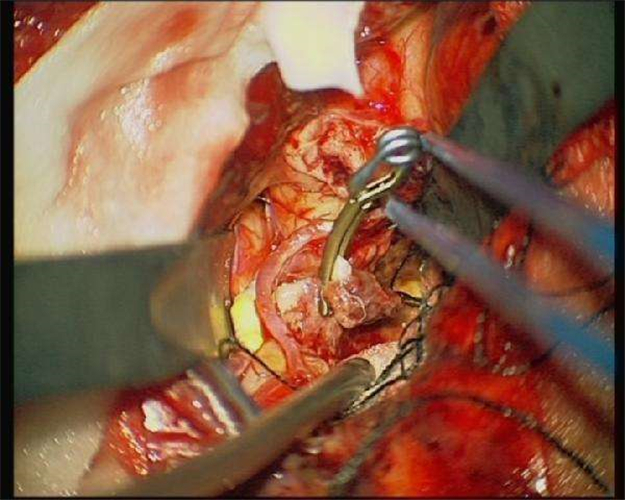

手術治療腦血管痙攣

手術治療腦血管痙攣的

手術治療腦血管痙攣合併動脈瘤

腦血管痙攣手術中